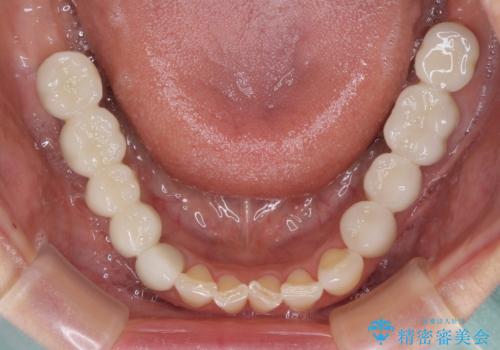

以前治療した歯がボロボロに 全顎補綴治療

- 以前治療した歯が欠けたり、痛みを感じたりしているとのことで来院された患者様です。

アメリカ国内を転々としながら治療を行ったため治療跡がモザイク様で、クラウンが壊れていたり、抜歯が必要であったりしていました。

上下左右すべての奥歯に処置が必要であり、同時に行うと食事が取りにくくなってしまったり、手前の歯に負担がかかって初診時よりも状況が悪化したりする可能性があるため、片方ずつ処置を進めて行くこととしました。

下顎右側は骨造成を併用してインプラント治療を行い、その他の奥歯もインプラントや歯周外科処置を併用して補綴治療を進め、最後に前歯部の欠けてしまったセラミッククラウンを作り替えることとしました。